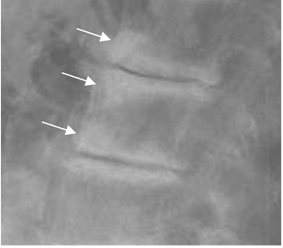

En las diferentes modalidades se aprecia como una indentación en la placa terminal, de bordes escleróticos, asociados o no a espondilosis y otros cambios degenerativos vertebrales. (27). (Fig 114 y 115).

La mayoría se localiza entre los cuerpos de T7 y L2, en la parte posterior y tienen predominio por la placa inferior. (27).

Fig 114. Nódulo de smorl.

A: Rx lateral. Irregularidad en la placa terminal superior.

B: TAC axial. Defecto de bordes escleróticos en la placa terminal, que corresponde a nódulo de smorl.